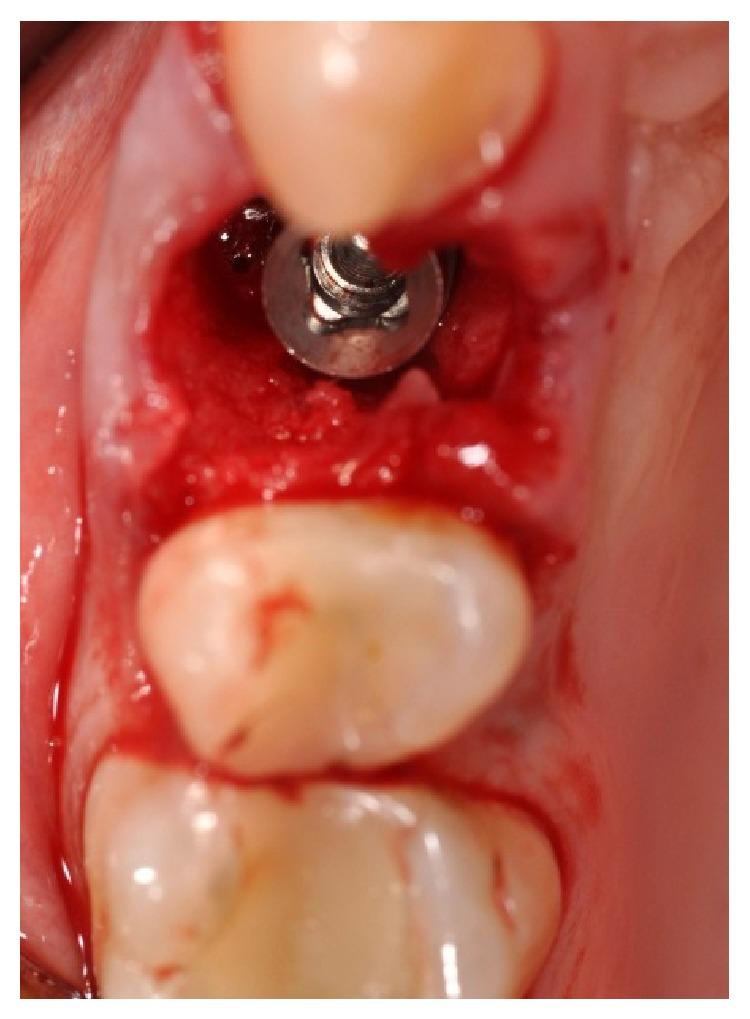

Aim. The aim of this work is to describe a case of immediate implant placement after extraction of the upper right first premolar, with the use of CAD/CAM technology, which allows an early digital impression of the implant site with an intraoral scanner (MHT 3D Progress, Verona, Italy). Case Report. A 46-year-old female was referred with a disorder caused by continuous debonding of the prosthetic crown on the upper right first premolar. Clinically, there were no signs, and the evaluation of the periapical radiograph showed a fracture of the root, with a mesial well-defined lesion of the hard tissue of the upper right first premolar, as the radiolucent area affected the root surface of the tooth. It was decided, in accordance with the patient, that the tooth would be extracted and the implant (Primer, Edierre implant system, Genoa, Italy) with diameter of 4.2 mm and length of 13 mm would be inserted. After the insertion of the implant, it was screwed to the scan abutment, and a scan was taken using an intraoral scanner (MHT 3D Progress, Verona, Italy). The scanned images were processed with CAD/CAM software (Exocad DentalCAD, Darmstadt, Germany) and the temporary crown was digitally drawn (Dental Knowledge, Milan, Italy) and then sent to the milling machine for production with a composite monoblock. After 4 months, when the implant was osteointegrated, it was not necessary to take another dental impression, and the definitive crown could be screwed in. Conclusion. The CAD/CAM technology is especially helpful in postextraction implant for aesthetic rehabilitation, as it is possible to immediately fix a provisional crown with an anatomic shape that allows an optimal healing process of the tissues. Moreover, the removal of healing abutments, and the use of impression copings, impression materials, and dental stone became unnecessary, enabling the reduction of the chair time, component cost, and patient's discomfort. However, it is still necessary for scientific research to continue to carry out studies on this procedure, in order to improve the accuracy, the reliability, and the reproducibility of the results.

目的。本研究旨在描述一例右上第一前磨牙拔除后即刻种植的病例,采用计算机辅助设计/计算机辅助制造(CAD/CAM)技术,该技术可通过口腔内扫描仪(MHT 3D Progress,意大利维罗纳)对种植部位进行早期数字化印模。病例报告。一名46岁女性因右上第一前磨牙修复冠持续脱粘导致的病症前来就诊。临床检查无异常体征,根尖片评估显示牙根骨折,右上第一前磨牙硬组织近中边界清晰的病变,因为透射区累及牙根表面。经与患者商议,决定拔除患牙并植入直径4.2毫米、长度13毫米的种植体(Primer,Edierre种植系统,意大利热那亚)。种植体植入后,旋紧扫描基台,使用口腔内扫描仪(MHT 3D Progress,意大利维罗纳)进行扫描。扫描图像用CAD/CAM软件(Exocad DentalCAD,德国达姆施塔特)处理,临时冠通过数字化方式绘制(Dental Knowledge,意大利米兰),然后发送至铣床用复合整体块制作。4个月后,种植体实现骨整合,无需再次取牙印模,即可旋入最终冠。结论。CAD/CAM技术在拔牙后种植的美学修复中特别有用,因为可以立即固定具有解剖形状的临时冠,有利于组织的最佳愈合过程。此外,无需移除愈合基台,也无需使用印模帽、印模材料和牙科石膏,从而减少了椅旁时间、部件成本和患者不适。然而,为了提高结果的准确性、可靠性和可重复性,仍有必要继续对此方法开展科学研究。